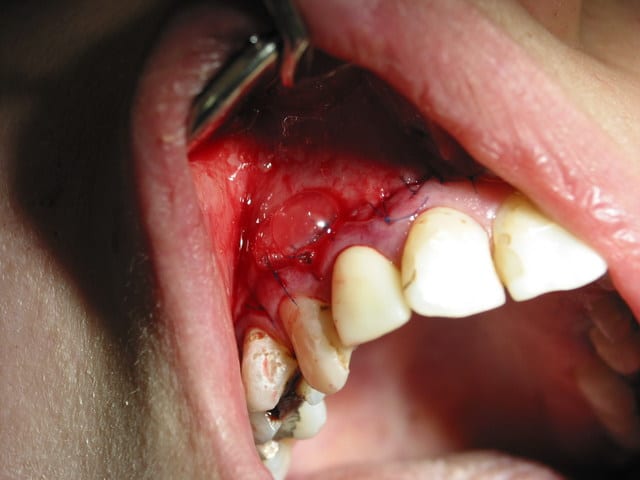

se presente a mon cabinet y a 2 jours envoyée par un confrere une jeune patiente prof qui se plaint d une "grosseur" au niveau de sa levre. Je zieute et je vous laisse voir la suite en images...

Pour athos : lambeau de pleine épaisseur biseauté à 3 mm du sulcus afin de préserver l'esthetique des couronnes. Lors du décollage, il apparait que la corticale externe a été soufflée complètement et qu'il n'en subsiste que des petits fragments "coquille d'oeuf" noyés dans un épais tissus fibreux réactionnel.

photo 2 en distal de la racine de 12 on voit l'enveloppe du kyste qui est crevé alors qu en mesial on voit encore la corticale sur 11. au dessus de la racine de la 12, tu peux voir le tissus fibreux et des petits éclats osseux qui sont les restes de la corticale externe. Ce kyste s'invagine jusqu'au plancher nasal et a mangé un peu la paroi du sinus en mésail de 13 rentrant en communication avec la membrane de schroeder. Lors du decollage de la membrane kystique, ces deux facias se sont parfaitement decollées l un de l autre (ouf). De l autre coté, j'ai decollé le kyste de lors du palais. Bref une belle cavité de plusieurs centimetres cubes.